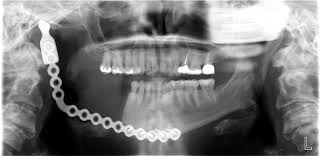

Robojaw 1 took place in February 2016. They removed half the mandible and replaced it with a titanium plate.

After six months or so of healing, Robojaw 2 occurred the day before Thanksgiving that same year. They wired my jaw shut for three weeks to keep the bone graft to rebuild the mandible fixed in place until it was hard enough for me to safely chew again.

Another six months gone by brings things to the present with step three. Dr. Marx removed four additional teeth in the lower front of my mouth. They would have eventually died from radiation treatment as well.

He also placed four implants below the jaw line. All this acts as a prelude to getting some teeth back in my mouth so I can chew food on that side, speak better, and prevent the upper right teeth from growing down and falling out since they have nothing to bite down on.

By next February the implants should have become integrated with the bone. They will affix posts to the implants. These will set above the jaw line.